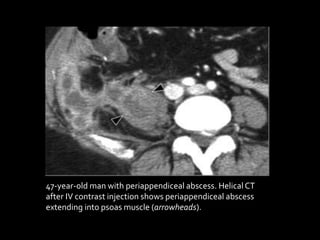

47-year-old man with periappendiceal abscess. Helical CT

after IV contrast injection shows periappendiceal abscess

extending into psoas muscle (arrowheads).

2.Periappendiceal Abscess

Abscess is the most frequent complication of

perforation.The abscess remains localized if

periappendiceal fibrinous adhesions develop

before rupture. CT shows a loculated, rim-

enhancing fluid collection that may have mass

effect on adjacent bowel loops. If the abscess is

large (> 4 cm), percutaneous drainage followed

by delayed appendectomy is the preferred

treatment .